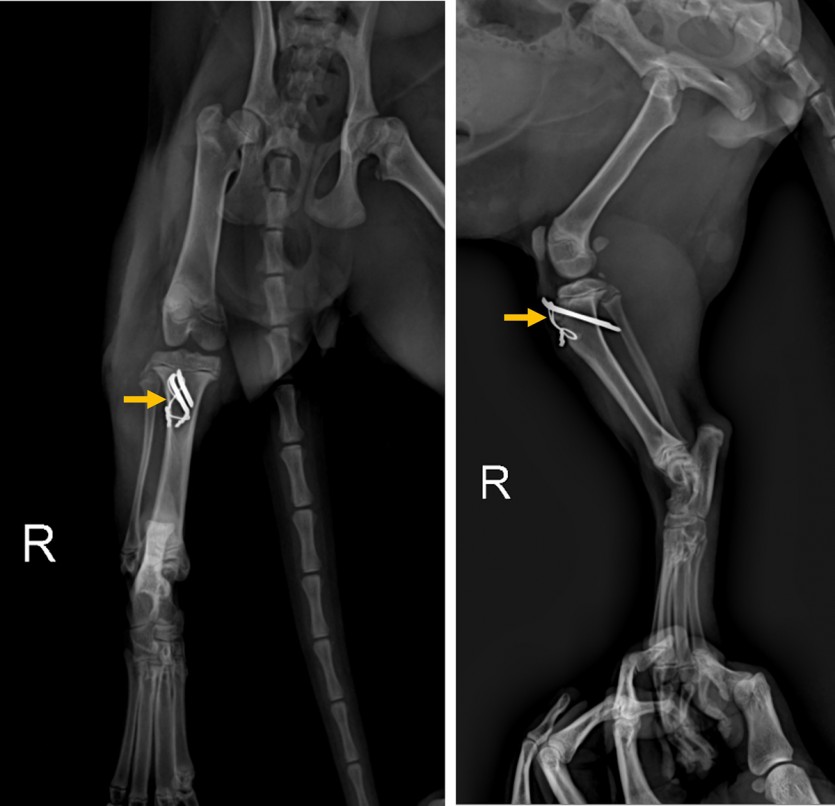

<수술 전 방사선 사진 : 좌측의 정상적인 경골조면(우측 사진 화살표)과 다르게 떨어져 나간 우측 경골조면(좌측 사진 화살표)이 확인된다>

방사선 촬영 결과, 우측 경골 조면의 박리 골절 (Tibia tuberosity avulsion fracture) 이 확인되었습니다.

경골조면에 부착하는 인대가 과도하게 잡아당겨지면서 골편이 위쪽으로 분리된 상황입니다. 골편의 이동이 큰 경우 당겨지는 힘, 견인력이 작용하기 때문에 외과적으로 수술을 해 주는 것이 필수적입니다.

5개월령의 어린 아이로 꼼꼼한 마취 전 검사가 진행되었고, 다행히 마취 전 검사 상에 아무런 문제가 없어 수술적인 교정이 진행되었습니다. 수술 중에 경골 조면의 골절선이 확인되었고, 골절선을 잘 맞춘 뒤 핀과 와이어를 이용해 단단하게 고정해주었습니다.

<수술 후 방사선 사진 : 핀과 와이어를 이용해 골절편 고정. 골절면이 잘 맞아 제 위치에 고정된 것이 확인된다>